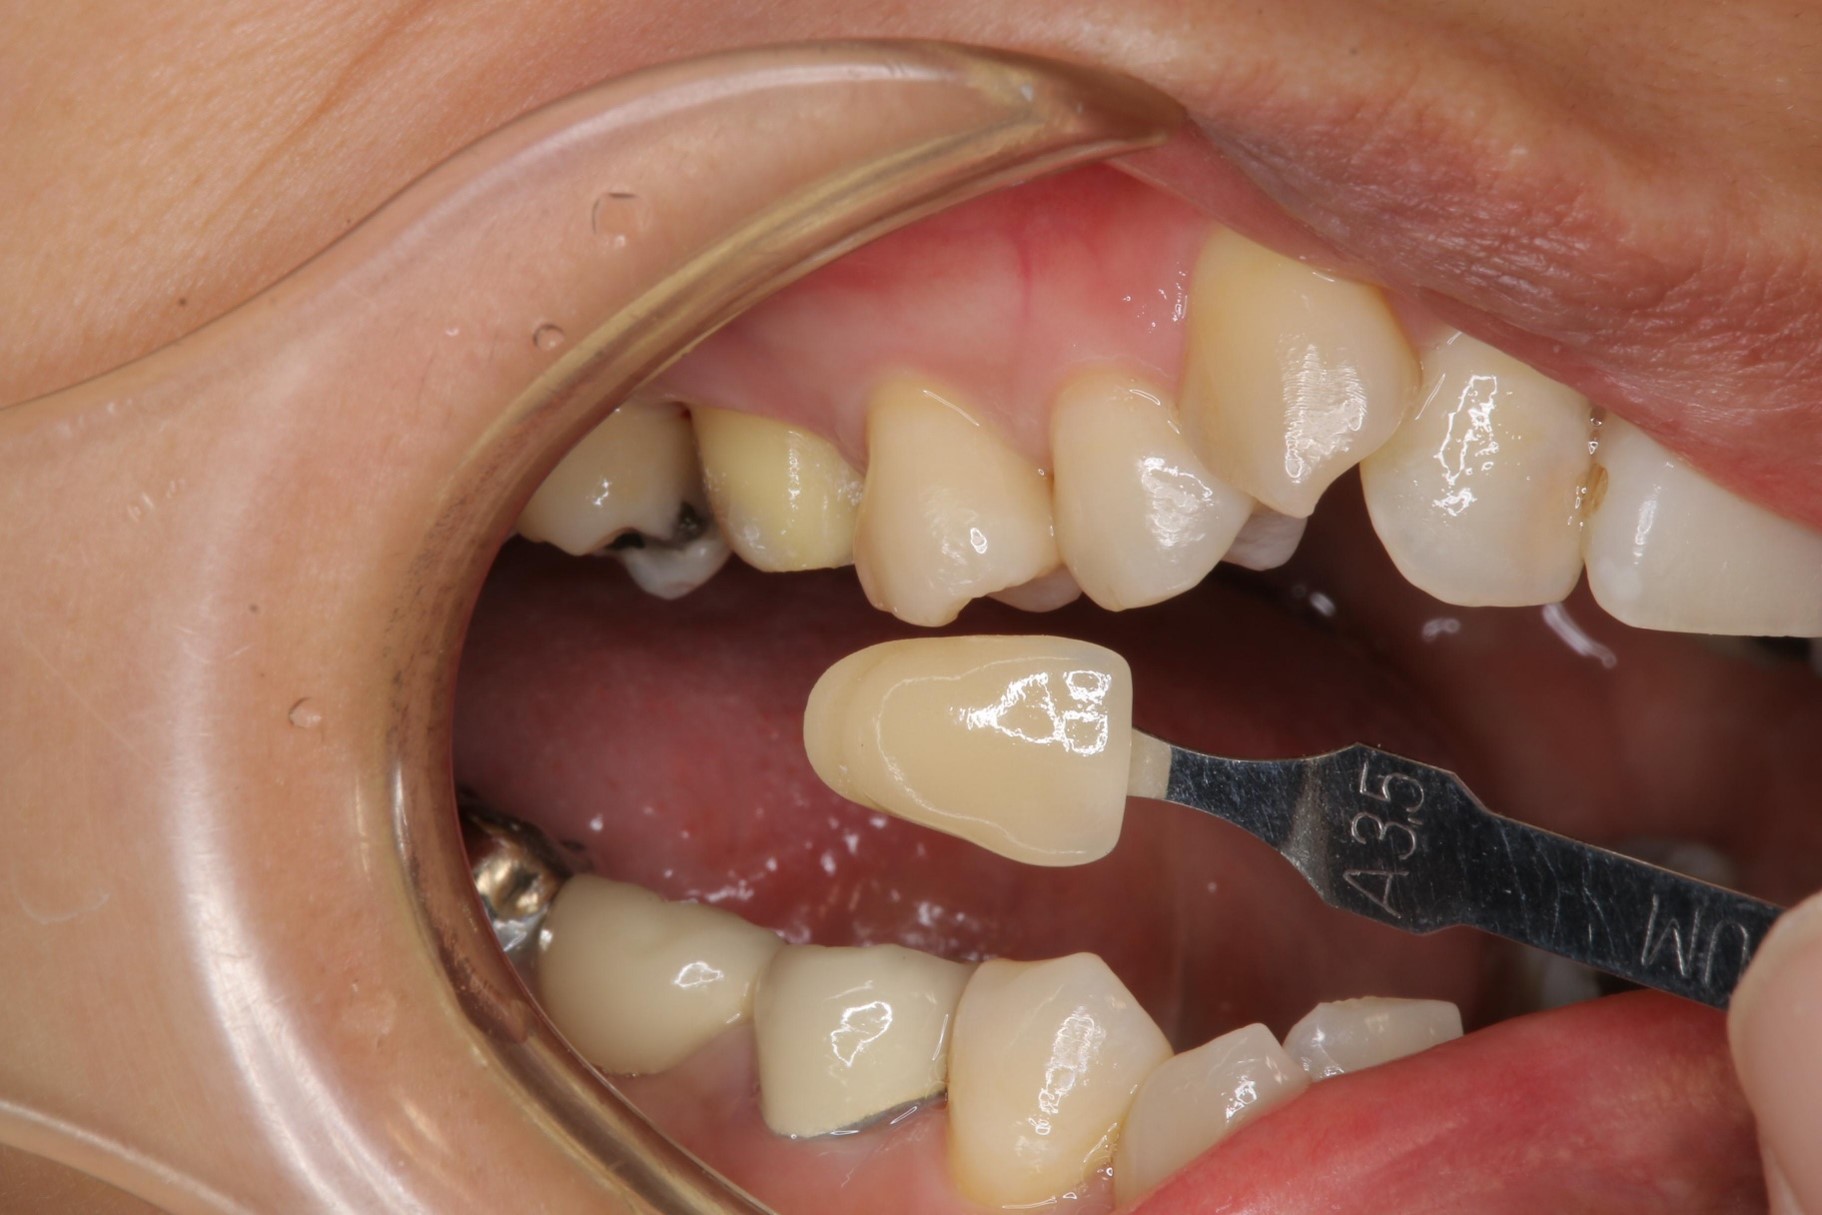

照相比色